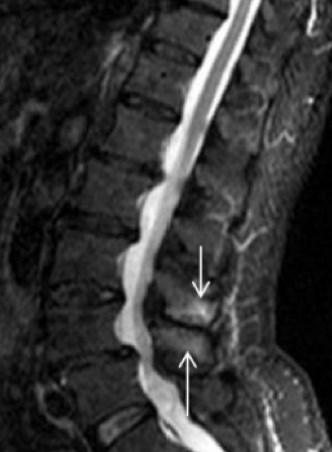

A diferencia de las tomografías computarizadas, una resonancia magnética puede detectar líquido bursal interespinoso y un quiste epidural posterocentral en las apófisis espinosas opuestas.

La bursitis interespinosa lumbar se diagnostica cuando hay líquido bursal entre dos apófisis espinosas afectadas opuestas.

Similar a una tomografía computarizada, la resonancia magnética muestra cualquier aplanamiento, esclerosis, agrandamiento, lesiones quísticas y edema óseo en las superficies articulares de las apófisis espinosas.

Este tipo de procedimiento de diagnóstico es extremadamente beneficioso para determinar si existe una compresión del saco tecal posterior como resultado de este contacto de los procesos interespinosos.

Otras ventajas de las imágenes por resonancia magnética también incluyen la ausencia de radiación ionizante y una imagen muy detallada a varios niveles (axial, coronal y sagital).